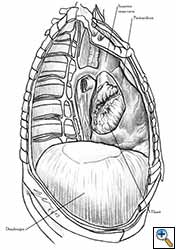

Medium and large-sized (Figures 1a, 1b) defects generally result after pneumonectomy for advanced central lung tumours which invade the pericardium (T3 invading pericardium), thus requiring reconstruction (Figure 1c). To achieve a curative resection, negative pericardial resection margins must be obtained and checked microscopically. More invasive tumours (T4 invading cardiac structures) require partial atrial resection and pericardiectomy associated with pneumonectomy.

|

| Figure 1c: Intraoperative aspect of pericardioplasty with Marlex mesh after right completion pneumonectomy with partial pericardiectomy. |